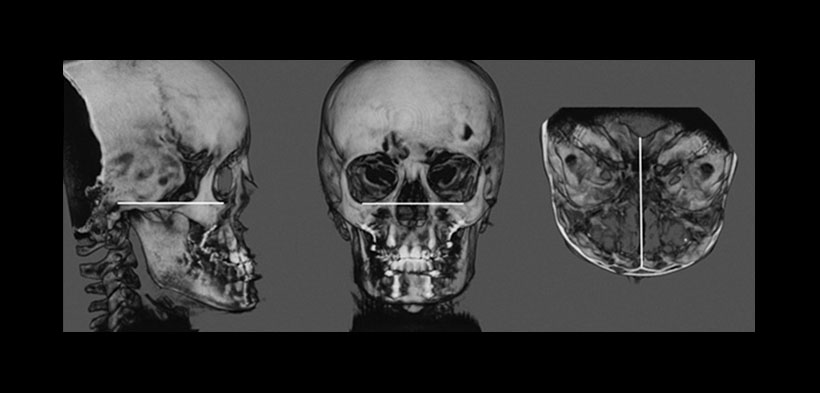

Fig. 2. Reconstruccion tridimensional el plano horizontal en referencia al plano de Frankfort. utilizando las siguientes líneas de referencia: (A) porion-orbitale en la vista sagital (B) trans-orbitale en la vista coronal, y (C) Crista Galli-medias de basion en el vista transversal.